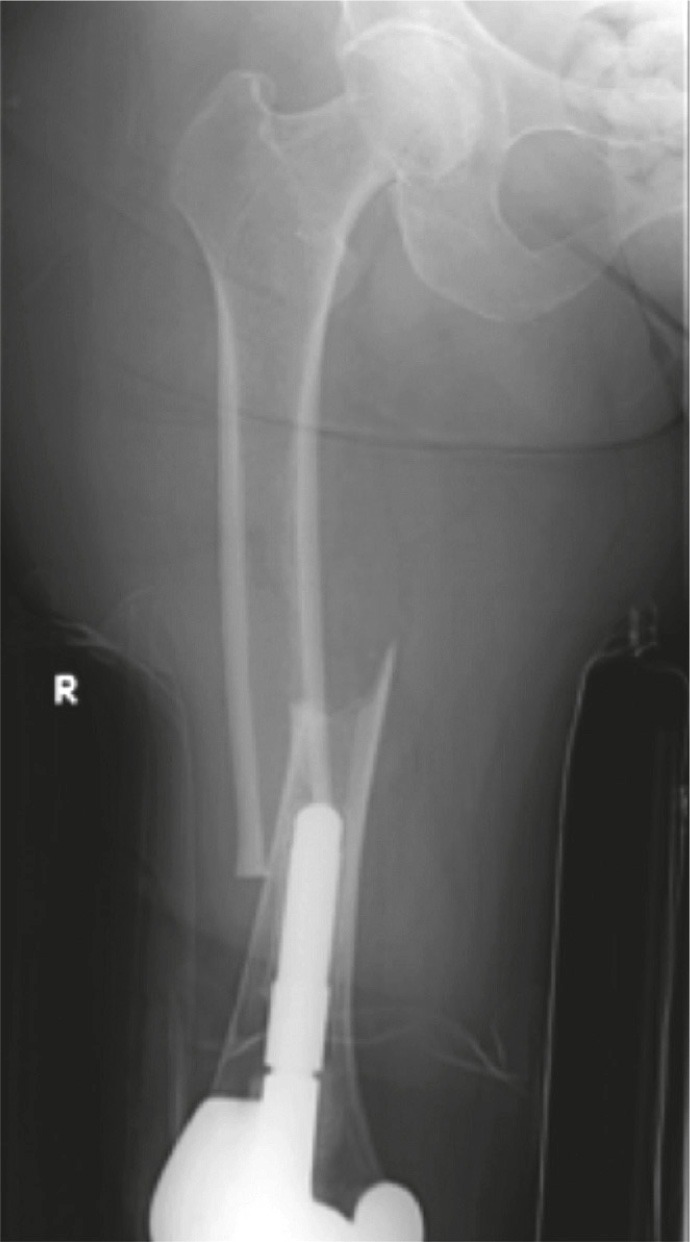

Figure 1.

Patient 6 (left panel). Medial spiking and lateral cortical thickening at the transverse fracture site.

In 8 of the injuries, the fracture line was at or just beyond the tip of the plate (Figure 2). In 3 of the injuries, the fracture was sustained through the second-most proximal screw hole of a plate. In 2 of these cases, the penultimate screw hole was the last functioning screw hole at the end of the plate (Figure 3). The fractures showed some radiographic features of atypicality such as (1) thickening of the lateral femoral cortex, (2) simple transverse or short oblique fracture pattern, and (3) absence of comminution.